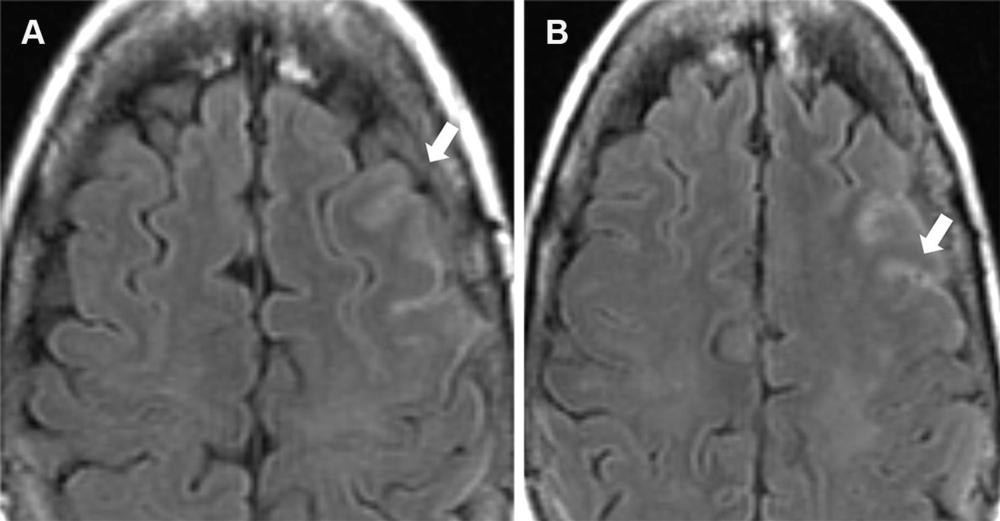

Figure 8. Mild ARIA-E (effusion) in a 62-year-old woman with mild cognitive impairment receiving aducanumab therapy. A baseline (pretreatment) MRI examination was unremarkable, and an amyloid PET examination (not shown) showed diffusely elevated amyloid. Contiguous axial FLAIR MR images obtained 9 weeks after initiation of therapy show sulcal hyperintensity (arrow) consistent with mild ARIA-E, and therapy was continued. Findings were stable at follow-up MRI after 1 month, with complete resolution after 3 months.

Figure 9. Mild ARIA-E (edema and effusion) in a 61-year-old man receiving aducanumab therapy. (A, B) Baseline pretreatment axial MR image (A) is unremarkable, with development of effusion (B) in the right occipital lobe (yellow arrow) and edema in the left occipital lobe (white arrow) on an axial MR image obtained 3 weeks after the target dose infusion (10 mg/kg). (C) Follow-up MR image after the fourth round of infusion shows near-complete resolution of the right occipital effusion (yellow arrow) with worsening of the left occipital lobe edema (white arrow). This was graded as mild throughout and therapy was continued, with complete resolution of all imaging changes at the seventh-week MRI examination.